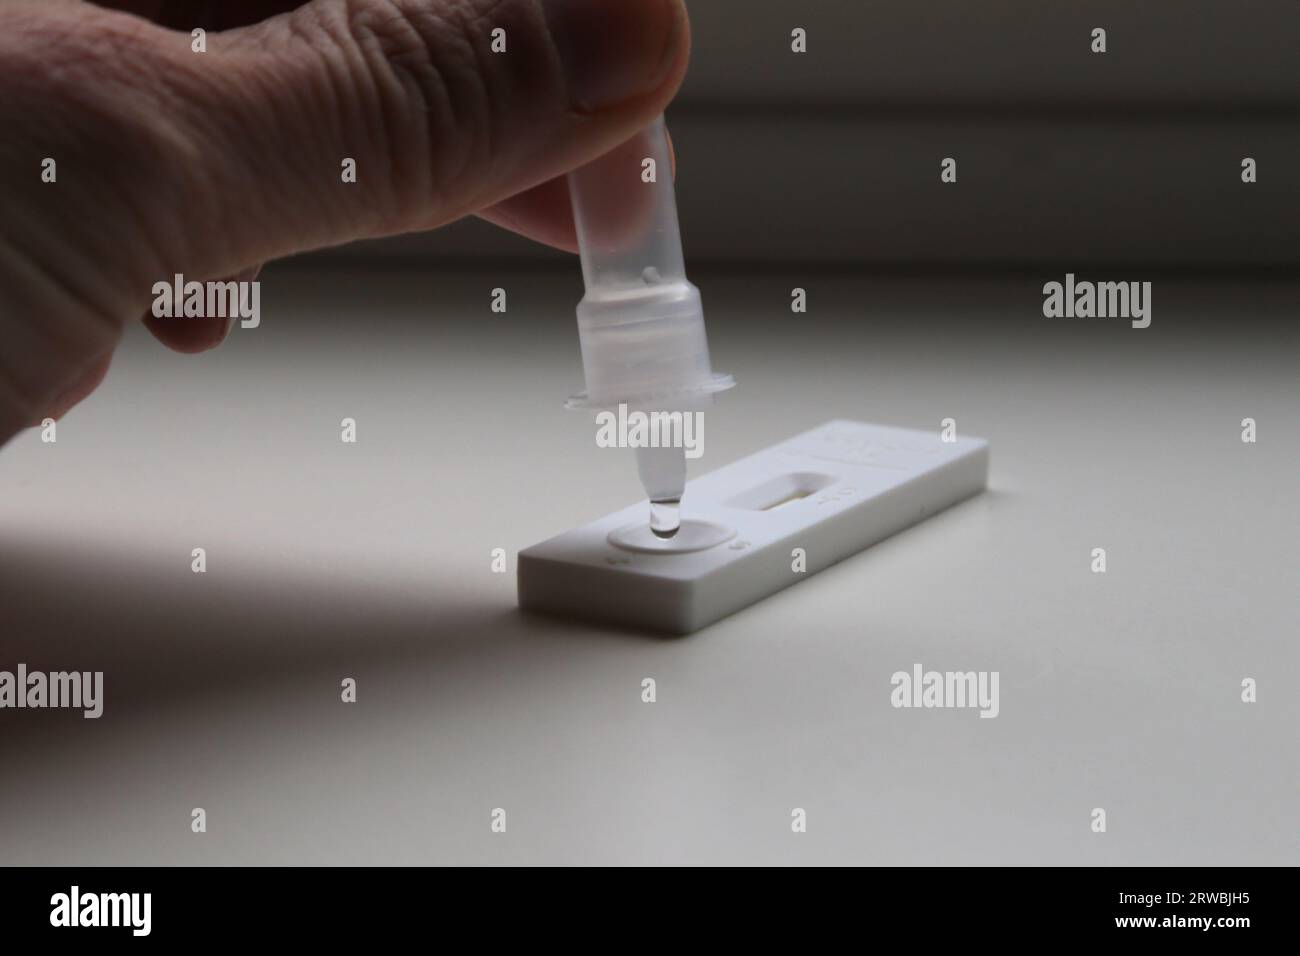

Corona antigen Rapid Test Kit, Self-test Stock Photohttps://www.alamy.com/image-license-details/?v=1https://www.alamy.com/corona-antigen-rapid-test-kit-self-test-image566354241.html

Corona antigen Rapid Test Kit, Self-test Stock Photohttps://www.alamy.com/image-license-details/?v=1https://www.alamy.com/corona-antigen-rapid-test-kit-self-test-image566354241.htmlRM2RWBJH5–Corona antigen Rapid Test Kit, Self-test

Corona antigen Rapid Test Kit, Self-test Stock Photohttps://www.alamy.com/image-license-details/?v=1https://www.alamy.com/corona-antigen-rapid-test-kit-self-test-image566354244.html

Corona antigen Rapid Test Kit, Self-test Stock Photohttps://www.alamy.com/image-license-details/?v=1https://www.alamy.com/corona-antigen-rapid-test-kit-self-test-image566354244.htmlRM2RWBJH8–Corona antigen Rapid Test Kit, Self-test

A medical, home covid test using antigen technology to check coronavirus antibody and keep people safe. Express health testing for covid 19 virus Stock Photohttps://www.alamy.com/image-license-details/?v=1https://www.alamy.com/a-medical-home-covid-test-using-antigen-technology-to-check-coronavirus-antibody-and-keep-people-safe-express-health-testing-for-covid-19-virus-image484480047.html

A medical, home covid test using antigen technology to check coronavirus antibody and keep people safe. Express health testing for covid 19 virus Stock Photohttps://www.alamy.com/image-license-details/?v=1https://www.alamy.com/a-medical-home-covid-test-using-antigen-technology-to-check-coronavirus-antibody-and-keep-people-safe-express-health-testing-for-covid-19-virus-image484480047.htmlRF2K45Y6R–A medical, home covid test using antigen technology to check coronavirus antibody and keep people safe. Express health testing for covid 19 virus